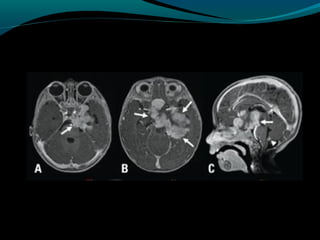

Astrocitoma pilomixoide

Semelhante ao pilocítico;

Comportamento mais agressivo;

Na infância pode ocorrer em qualquer estrutura do

SNC mas predomina no hipotálamo;

Precoce, crianças de 18 meses;

Pode acometer adultos mais frequentemente;

Sintomas: achados de aumento da pressão

intracraniana e compressão encefálica;

Retardo no desenvolvimento, vômitos, dificuldade de

alimentar-se ou aumento do perímetro cefálico;

Hipotalâmica;

TC

Lesão expansiva sólida na região hipotalâmica

quiasmática;

Isodensa ou hipodensa; realce difuso;

calcificação <10% dos casos;

Hemorragia é mais comum quando comparado ao

pilocítico;

RM

Isointenso ou hipointenso em T1 e hiper em T2 e

FLAIR, realce pelo gadolíneo;

Regiões com alto sinal em T1 (hemorragia);

Componente cístico 50%

Disseminação leptomeníngea em até 15%;

Difusão: não tem restrição à difusão da água (DD:

PNET, germinoma, linfoma);